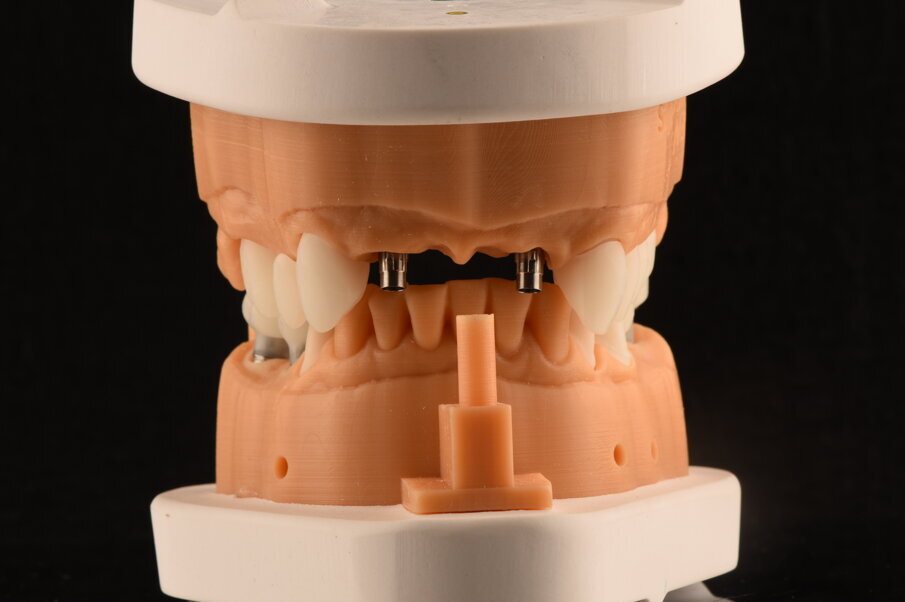

Fig. 33_Modelli realizzati in resina e montati in articolatole a valori medi.

Fig. 34_Dettaglio del modello superiore con la visione palatale, con i monconi t-base da ancoraggio per elementi CAD/CAM.

Fig. 45_Il modello digitale rappresenta un mezzo per presentare il restauro nel progetto. È eseguito a computer e solo alcune modifiche vengono fatte, come l’aggiunta di ceramica per enfatizzare l’aspetto estetico. Altro significato è deputato alla precisa posizione degli analoghi implantari.